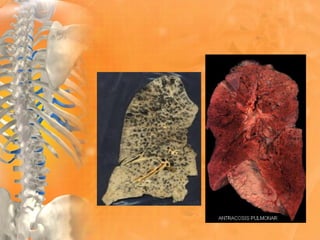

Por el tipo de trabajo.

• Saturnismo → Pb

• Asbestosis → asbesto

• Calcicosis → Ca

• Pneumoconiosis → carbón

OCUPACIONALES